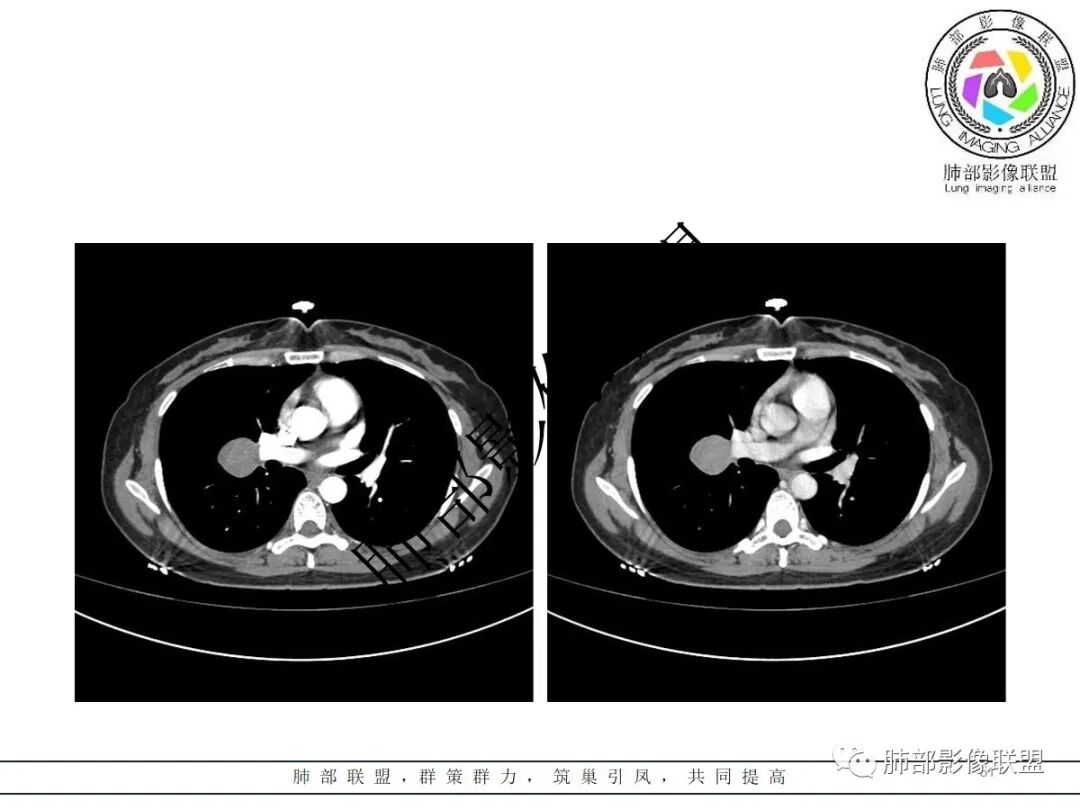

右肺门类圆形实性肿块,边缘光滑,无分叶毛刺,跨叶,推移血管,密度均匀,增强延迟强化相对明显,未见坏死及血管造影征。

3.病灶密度均匀,未见液化坏死、钙化及脂肪低密度。轻度强化,可见纤细血管影蜿蜒穿行。右肺动脉推移变形,未见侵入或充盈缺损。

1)巨淋巴结增生症(CD)大多动脉期高强化,毕竟透明血管型占多数,本例特征不足。

3)硬化性肺细胞瘤(PSP)可以血管贴边,常常强化比较显著。

4)发生于肺表面(近脏层胸膜或叶间裂),强化不显著,可见穿行血管,与本例的符合程度是最高的。

3)CT増强多呈中度至明显均匀强化,多期扫描呈持续性强化,部分病灶早期强化不均匀,呈花斑状,延迟后强化较早期均匀;

4)瘤周可出现晕征、空气新月征及贴边血管征,若同时出现,诊断PSP的信心更好。